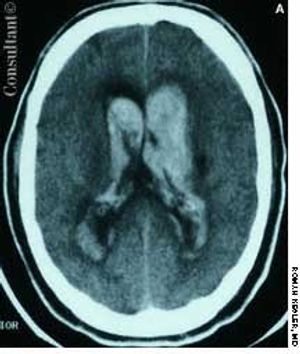

A 57-year-old man complained of a severe headache of sudden onset while he was lifting heavy boxes. Within minutes, he collapsed and became unconscious. On arrival at the emergency department, the patient was deeply comatose. His pupils were 7 mm, fixed, and unreactive to light; brainstem reflexes were absent, and he was unresponsive to noxious stimulation. His blood pressure was 210/120 mm Hg; he had no known history of hypertension.